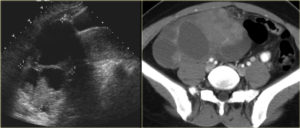

- Ультразвуковая диагностика. В ходе проведения исследования есть возможность точно определить структуру образования, его размеры и расположение. Также УЗИ позволяет увидеть какая структура преобладает внутри кисты и сделать вывод о принадлежности ее к одному из видов. Но данный вид исследования не позволяет определить к доброкачественной или злокачественной относится опухоль. Именно эта информация позволяет назначить эффективное лечение.

В остальных случаях на помощь приходят методы медицинской визуализации — УЗИ, КТ, МРТ, рентгенологическое исследование, ПЭТ, эндоскопическое исследование и другие.